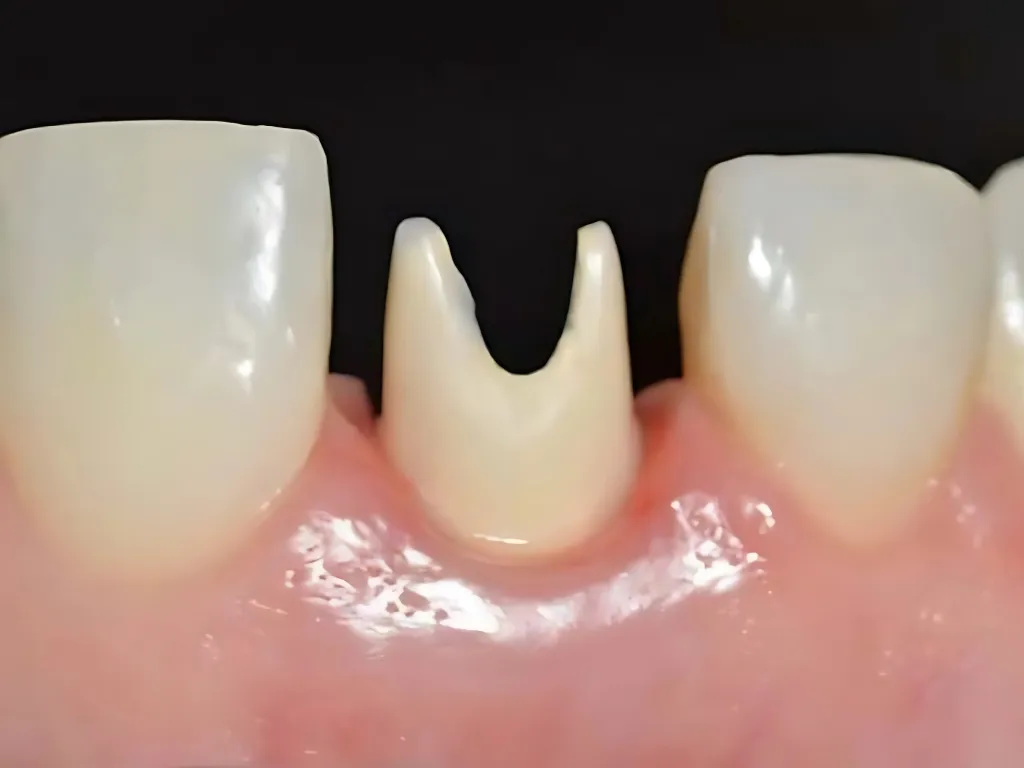

vaka_img

Immediate Geçici Protez Yüklemesi

Dr. Maurice Salama